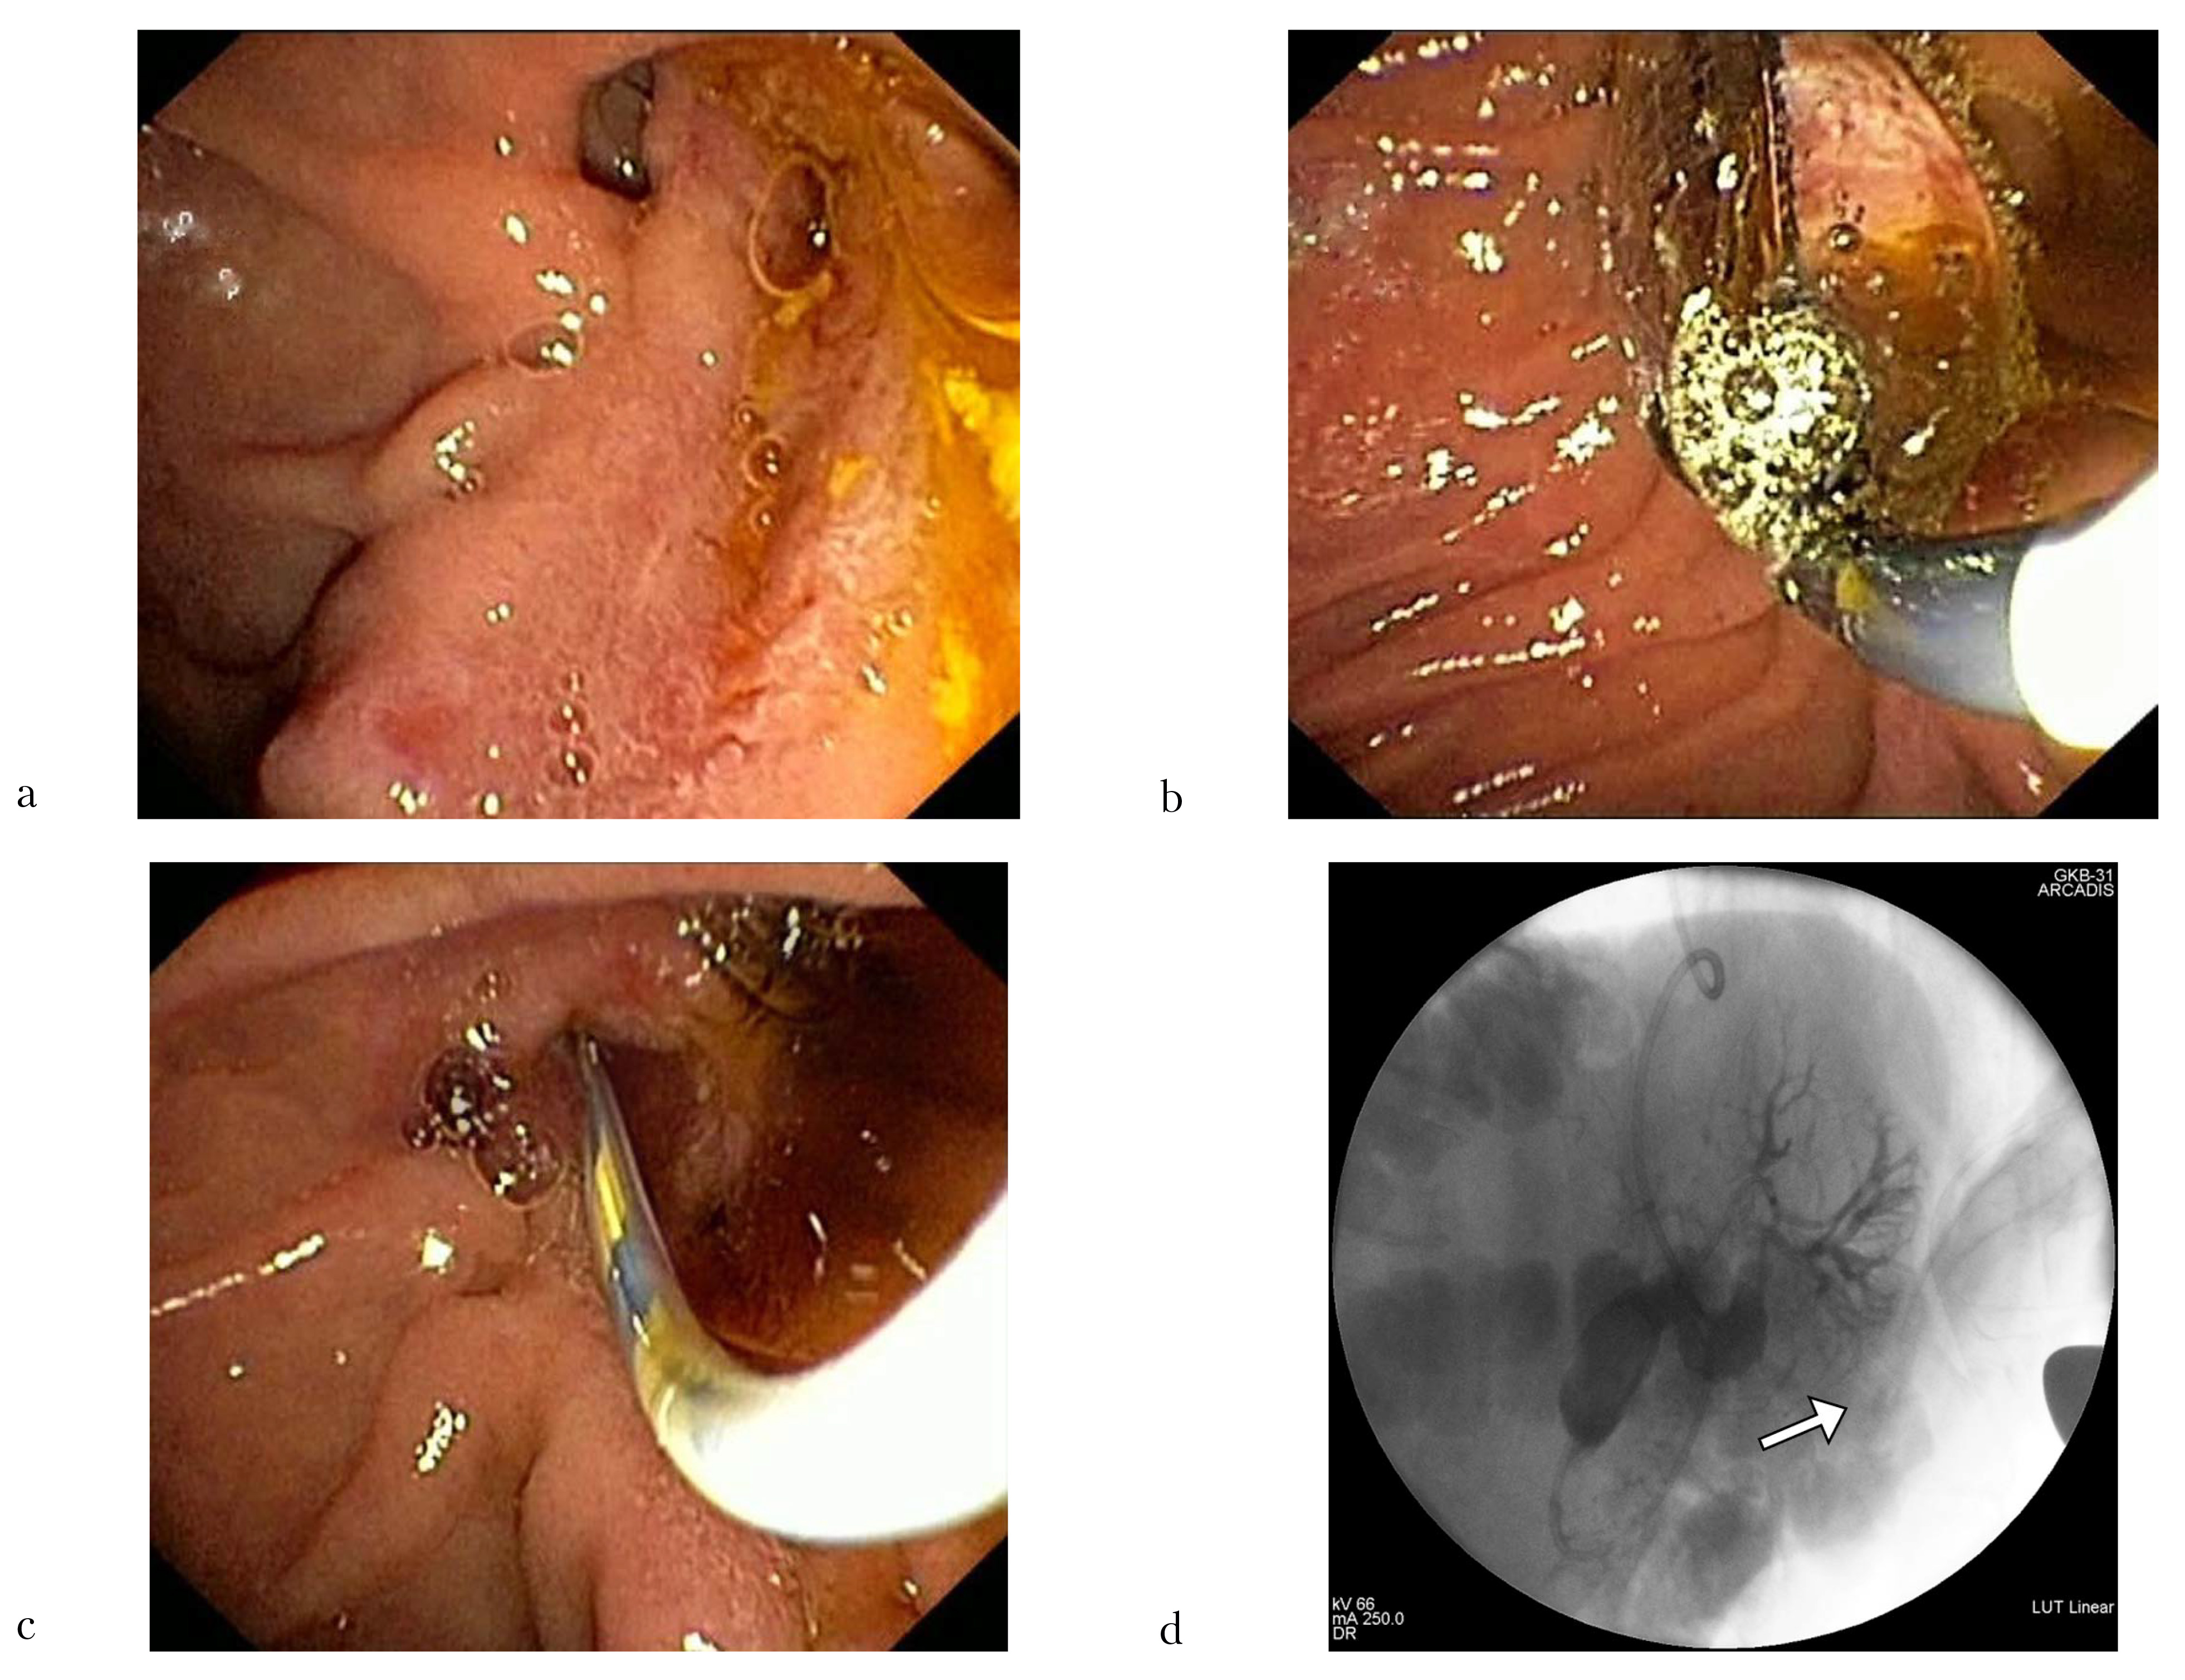

С помощью баллона диаметром 13–14–15 мм и длиной 5 см фирмы Boston Scientific (США) была успешно осуществлена баллонная дилатация области ЭПСТ (рис. 2a–c). Однако попытка механической литотрипсии оказалась безуспешной ввиду невозможности завести литотриптор выше конкремента и захватить его. Учитывая интраоперационную ситуацию, а также наличие клинико-эндоскопических проявлений острого холангита, было принято решение о выполнении назобилиарного дренирования и проведении дистанционной ударноволновой литотрипсии (ДУВЛ) после разрешения клинической картины холангита (рис. 2d).

Рис. 2: a — устье холедоха до баллонной дилатации (эндофото); b — баллонная дилатация (эндофото); c — устье холедоха после баллонной дилатации (эндофото); d — назобилиарный дренаж, установленный в просвет ОЖП, где в дистальных отделах определяется крупный конкремент — указан стрелкой (холангиограмма)